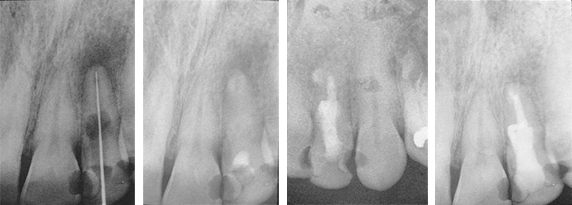

- For complicated cases involving traumatic injury and other instances where extended calcium hydroxide therapy is indicated.

- Treats periapical lesions, abscesses, traumatic injuries, root resorption, root perforations, and weeping canals

- Stimulates apexification and apexogenesis